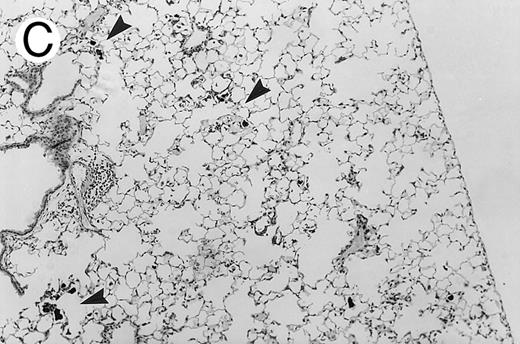

Three groups of X-CGD mice were studied: (1) control X-CGD mice; (2) X-CGD mice challenged 10 to 14 weeks after transplantation with MSCV-91Neo–transduced X-CGD BM; and (3) X-CGD mice challenged 5 to 8 weeks after transplantation with mixtures of wild-type and X-CGD BM cells. The results are summarized in Table 2. There were no deaths during the 17 to 21 days after challenge except for one mouse in the second group who died of complications of anesthesia on day 1. All 16 control X-CGD mice that were not transplanted developed lung disease after respiratory exposure to A fumigatus conidia. A common finding in lung tissue was the presence of multiple foci of granulomatous microabscesses that also contained occasional giant cells (Fig 3A). Rare hyphae were also seen. Larger inflammatory nodules containing numerous neutrophils and hyphae were seen in some mice (Fig 3B). Large abscesses with necrotic centers or regional bronchopneumonia were also occasionally observed (not shown). In 4 of 4 X-CGD mice transplanted with marrow transduced with the low-titer MSCV-h91Neo vector, who had only 1% to 2% NBT+ PB neutrophils at time of challenge, lung disease similar to that seen in untransplanted X-CGD mice was seen (Table 2). However, only minimal, if any, inflammatory changes were seen in 9 of 9 X-CGD mice with ≈50% to 80% NBT+ circulating neutrophils after transplantation with BM transduced with the high-titer vector (Table 2). Lungs appeared either normal (except for macrophages containing colloidal carbon that was administered along with conidia to mark the site of delivery) or contained occasional collections of mononuclear cells, typically in perivascular or peribronchial locations (Fig 3C). These findings were similar to those seen in lungs of wild-type mice after challenge with these numbers of A fumigatus conidia (unpublished observations, 1996).

Pulmonary findings 17 to 21 days after intratracheal instillation of A fumigatus conidia in X-CGD mice. Lung tissue was obtained 17 to 21 days after intratracheal challenge with 150 to 500 A fumigatus conidia, and stained with hematoxylin and eosin (A and C) or Grocott methamine silver (B). Representative photomicrographs obtained from three different mice are shown (original magnification × 100). (A) Untransplanted X-CGD mouse. Granulomatous microabscesses are seen, with occasional giant cells. (B) Untransplanted X-CGD mouse. Large inflammatory nodules with a central collection of neutrophils and numerous hyphae are seen. (C) X-CGD mouse transplanted with marrow transduced with the high-titer MSCV-m91Neo retrovirus. Occasional mononuclear cells in perivascular spaces and alveoli are seen, along with macrophages containing colloidal carbon (arrows) that was administered with the conidia to mark the site of delivery.